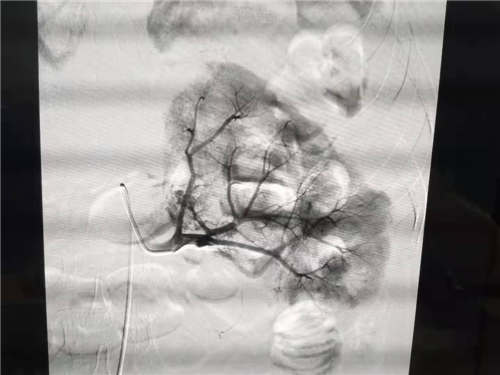

患者邓某,女,54岁,因突发左侧腰部疼痛1天入住小艾电竞社区 普胸泌尿外科,经增强CT检查诊断为左肾血管平滑肌脂肪瘤伴出血。为止血及切除肿瘤,因传统的开腹手术创伤大,术后恢复慢,而微创介入手术相对止血较彻底,创伤小,普胸泌尿外科决定由放射科实施左肾肿瘤栓塞术。术后患者血管减影出血停止,肿瘤栓塞成功,患者病情稳定,病人无需再行外科手术。

此栓塞法即可治疗肿瘤破裂出血,又可使肿瘤完全栓塞,因此为安全、微创、治疗破裂出血的有效方式。